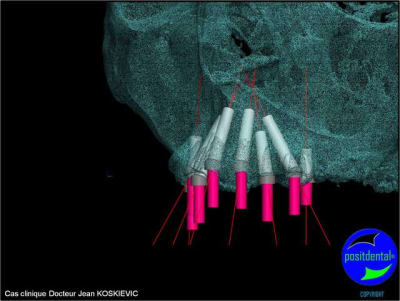

3D maxillaire inférieur et photo

et la projet 10 implants maxillaire sup

10 en haut

donc ce sera minimum 8 en fonction du scan